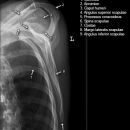

Scapula p.a. , liegend oder stehend (ventro-dorsal)

Darstellung der Scapula, wobei diese in ihrem medialen Teil von den Rippen überdeckt wird, sowie die Gelenkpfanne des AC-Gelenks. Durch starke Abduktion des Arms kann die mittlere Scapulaspitze von den Rippen frei projiziert werden.

Indikation und Beurteilungskriterien

Habituelle Luxation, gute Beurteilbarkeit der Relation zwischen Humeruskopf zur Glenoidpfanne.